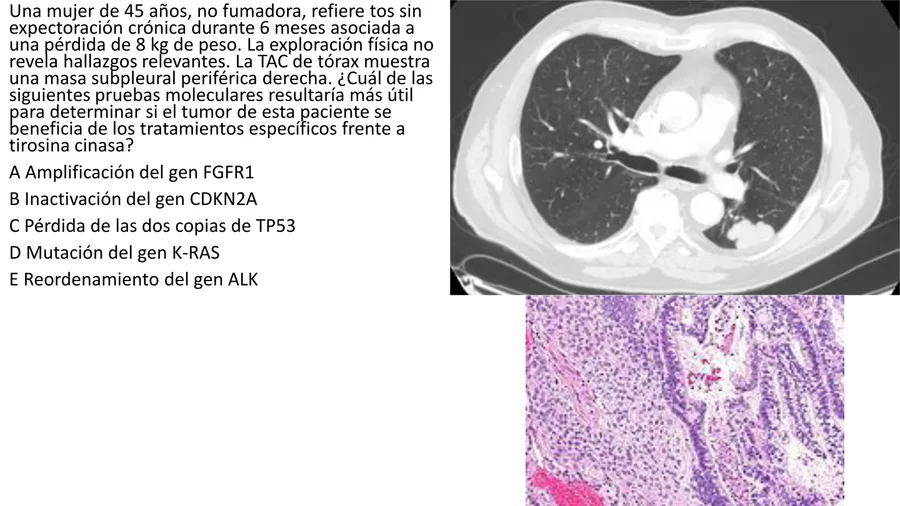

Multiple Choice

¿Cuál de las siguientes alteraciones genéticas es característica del carcinoma de células pequeñas de pulmón?

Pérdida de la función de TP53

Mutación en EGFR

Translocación ALK

Mutación en KRAS